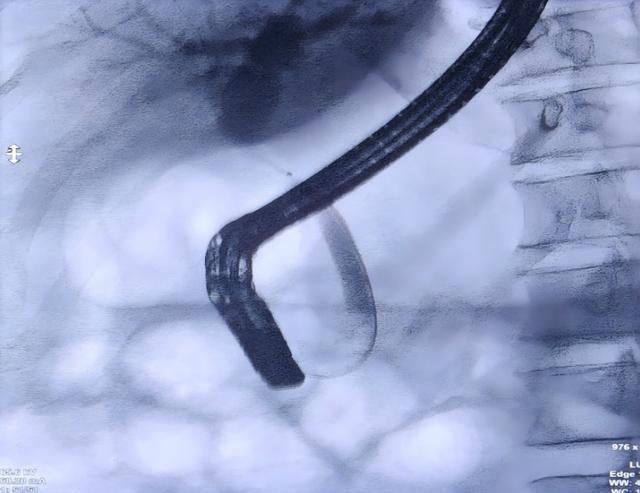

通过子镜观察到患者胆总管上段存在一处长约1cm的狭窄并增厚胆管壁,并在病变部位精准钳取3块组织样本。果然,病理报告提示腺癌,这一结果证实了专家团队的初步判断。

该团队在国内内镜诊疗领域处于领先地位,常规开展胆道子镜检查、经内镜逆行胰胆管造影术(ERCP)、超声内镜(EUS)等复杂操作,为胆管狭窄、胆道结石及胆胰肿瘤等疾病患者提供精准诊断与治疗。